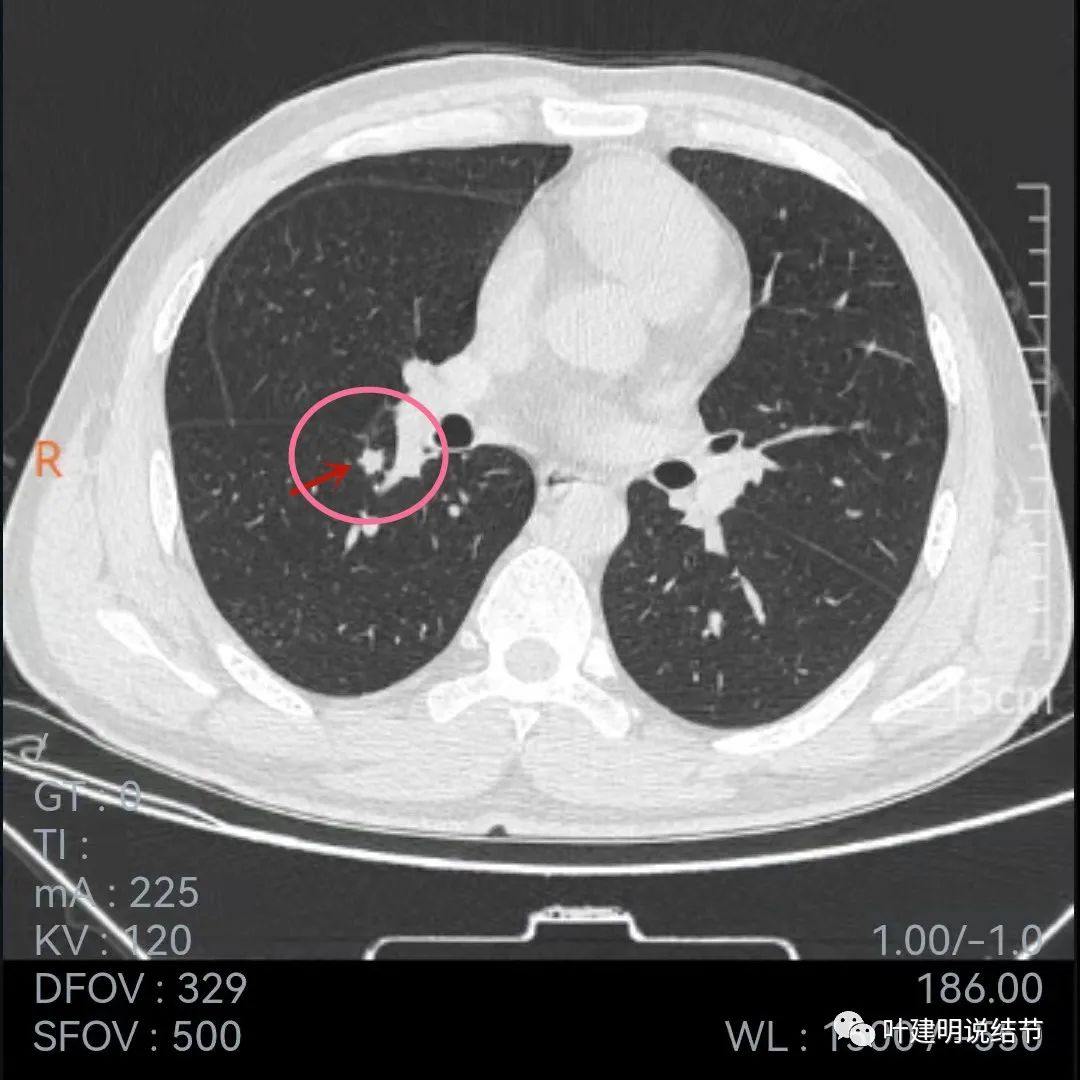

再看今年9月份的平扫片子:

也是三个层面可见,较去年也许略有增大,但测量起来可能差别不大,因为也是6-7毫米许。

再来看薄层的,今年的薄层是1毫米一层的,去年是2毫米:

病灶胸膜凹陷更明显了,边缘不太平整(紫色箭头)

胸膜牵拉,伴病灶中间密度稍低

病灶膨胀性不够,感觉刺突相对较长,中间密度略低,边缘向内凹

上图黄色箭头示病灶中间密度要略低于周边部位,这与肉芽肿较为符合

整体还病灶似有进展,形态略有变化,但说典型的恶性样子好像又不太像。